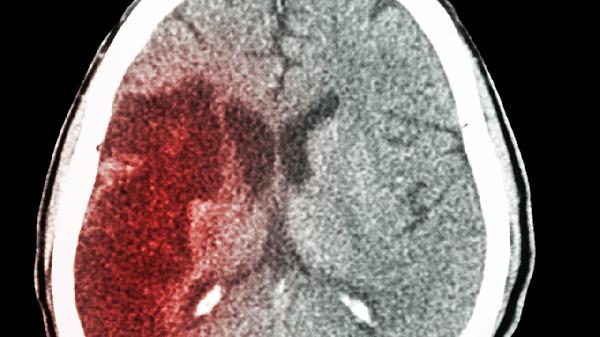

CT检查是主要鉴别手段。脑出血显示为脑实质内高密度影,边界清晰;蛛网膜下腔出血可见脑沟、脑池内铸型高密度,需通过脑血管造影进一步明确责任血管。